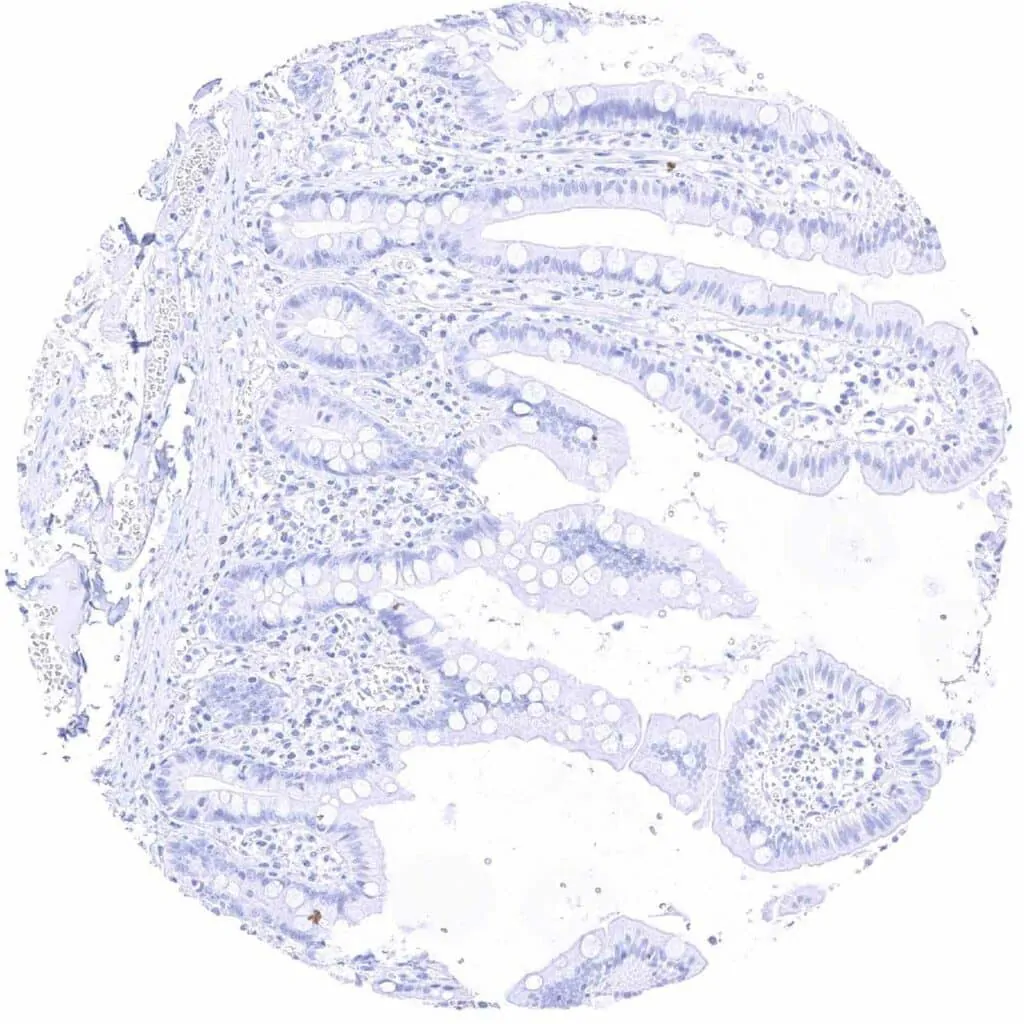

Duodenum, mucosa

Ileum, mucosa